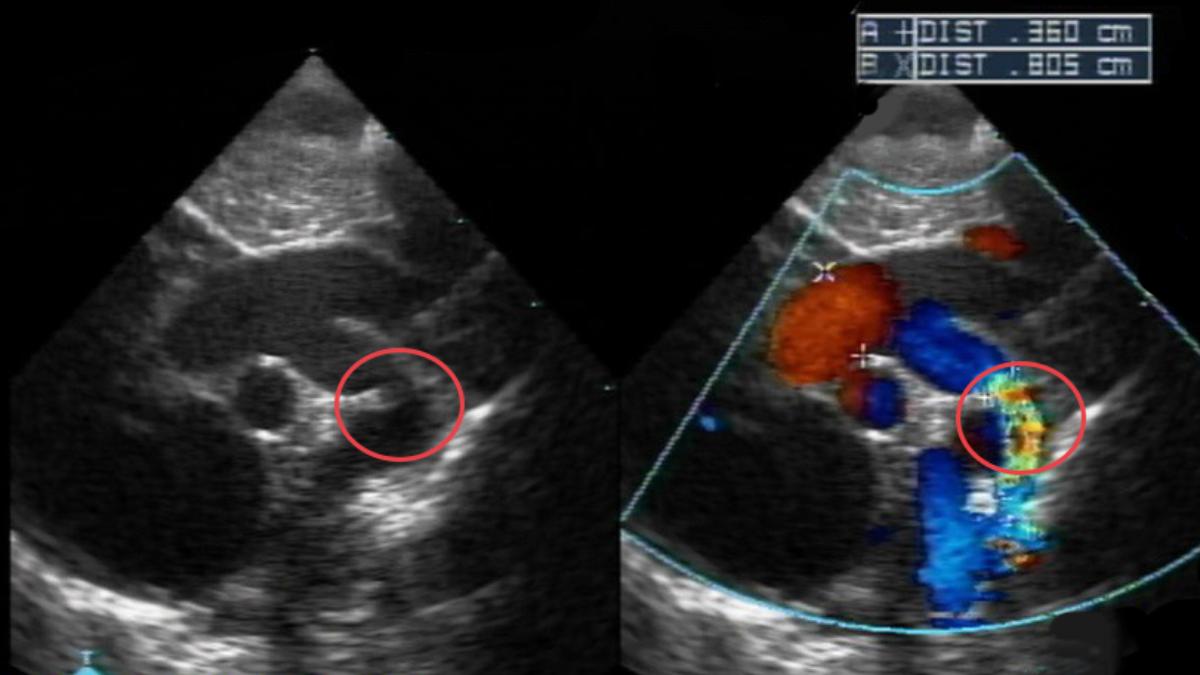

據澄清醫院中港分院小兒心臟科主任何季麟說明,該男寶寶出生時沒有任何症狀,但家長保險起見,替愛子進行新生兒自費超音波檢查,原本是想做全面健檢,結果意外找到男寶寶主動脈弓有一明顯縮窄處,確認是萬分之四發生率的「主動脈弓縮窄」,何季麟解釋,通常因為在母親肚子裡狹窄不明顯,所以會於出生後發病,又可再分為嬰兒型跟成人型。